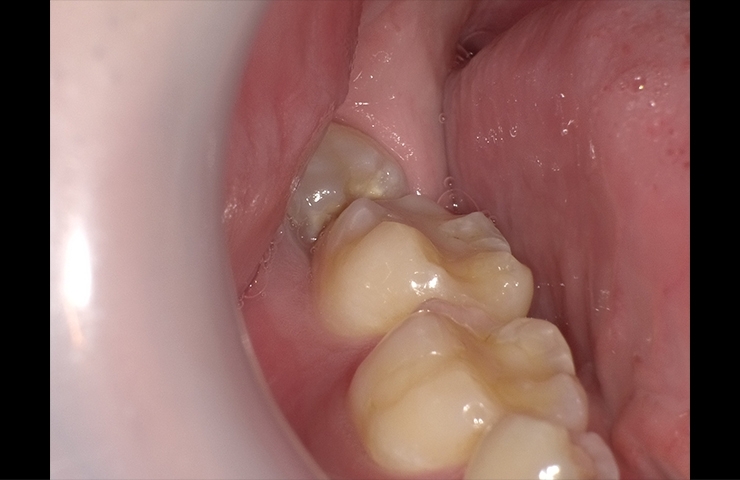

親知らずの抜歯の症例 恵比寿の歯医者 歯科 無痛治療が評判の五十嵐歯科医院 恵比寿駅2分

17 12 6 こんな珍しい親知らず 高槻 えむら歯科 と申します

衝撃の親知らずの根っこ スタッフブログ 愛媛県松山市伊藤歯科医院